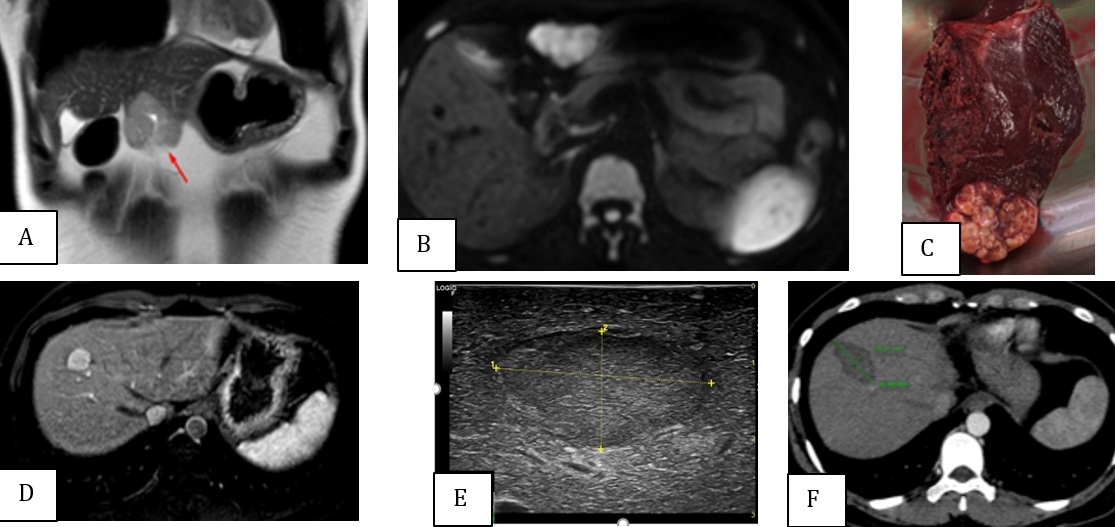

Figure 2 : Femme, 34 ans, hépatites B. Découverte fortuite de deux CHC au segment III, hypersignal en T2 (A) et en DWI (B), et au segment VIII, hypervascularisé en phase artérielle (D). AFP initiale de 2334 ng/ml. Résection de la lésion du segment III (C) et RFA peropératoire de tumeur du segment VIII, sous-échographie (E). Contrôle par TDM après un mois sans rehaussement (G), AFP réduire de 18,07 ng/ml.